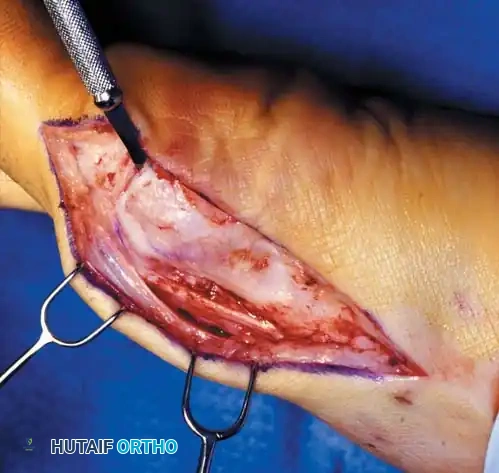

Modifi ed McBride Bunionectomy TECHNIQUE 78-1

SKIN AND CAPSULAR INCISION

• With the patient supine and a tourniquet on the limb, extend a midline, straight, medial incision from the middle of the proximal phalanx to 2 cm proximal to the junction of the medial eminence with the metatarsal shaft (Fig. 78-13). This incision usually is in an internervous plane between the most medial branches of the superfi cial peroneal nerve dorsally and the medial proper digital branch of the medial plantar nerve plantarward. (McBride recommended a single incision beginning at the fi rst web space and extending proximally and medially across the metatarsal, ending on the medial side of the fi rst metatarsal proximal to the exostosis.)

• Mobilize the skin 2 to 3 mm dorsally and plantarward to ensure that no sensory nerve would be injured by the capsular incision.

• Coagulate the superfi cial veins as encountered to minimize postoperative bleeding.

• Use delicate, two-tooth retractors and 1.5-mm forceps in this initial dissection to avoid unnecessary skin trauma.

• Make a longitudinal capsular incision (the original McBride capsular incision was transverse) 3 to 4 mm plantar to the line of the skin incision (Fig. 78-14).

• By sharp dissection, raise the periosteum and the capsule dorsally and plantarward from the base of the proximal phalanx to the proximal edge of the medial eminence (Fig. 78-15). At the proximal end of the medial eminence, avoid releasing the proximal bony attachments of the medial capsule on the metatarsal neck (especially in the dorsal direction) in an attempt to expose the medial eminence. To ensure adequate exposure without disruption of this proximal attachment, a longitudinal capsular incision is suggested.

• Elevate the capsule by sharp dissection dorsalward and plantarward to expose the dorsal aspect of the metatarsal head, the entire medial eminence, and the plantar plate. A periosteal elevator is not recommended because of the possibility that the proximal attachments of the capsule may be released.

L-SHAPED CAPSULAR INCISION

• Alternatively, make the capsular incision in an inverted L shape (Fig. 78-16A).

• Raise the dorsal fl ap deep to the nerve and veins until the accessory slip of the extensor hallucis longus tendon is seen in the proximal portion of the incision where it is easier to identify. The tendon almost always can be located with careful searching. If it is not seen at the dorsomedial aspect of the fi rst metatarsal, however, begin the longitudinal limb of the incision at this slope of the metatarsal from dorsal to medial.

• Begin the incision proximally on the dorsomedial side of the fi rst metatarsal shaft and 2 to 3 mm medial to the accessory slip of the extensor hallucis longus tendon. Carry the incision to the bone at the level of the fi rst metatarsal joint, extending proximally 4 to 6 cm.

• Make the transverse limb of the capsular incision at the level of the joint, stopping 2 to 3 mm from the tibial sesamoid bone; this limb transects the capsular insertion of the abductor hallucis muscle (Fig. 78-16B and C).

Fig. 78-15 Modifi ed McBride procedure. Capsule is opened, and attachment of capsule on metatarsal neck (arrow) is carefully preserved.

• Beginning on the plantar aspect of the incision, remove the capsule from the medial eminence from the inside out. Avoid buttonholing the capsule at the junction of the medial eminence and the metatarsal by directing the small-bladed knife down the slope of the eminence.

• Free the capsule subperiosteally on its dorsomedial surface, and retract it proximally and plantarward (Fig. 78-16D).

• Insert one small Hohmann retractor over the dorsolateral surface of the metatarsal head and another beneath the head at the head and neck junction, while distracting and plantar fl exing the hallux to expose the articular surface of the metatarsal head for evaluation of its condition and orientation. Reduce the hallux congruently on the metatarsal head.